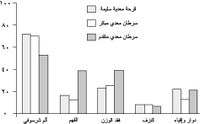

يشاهد سرطان المعدة غالباً في الأعمار المتقدمة، وتختلف نسب الإصابة به بحسب الجنس، إذ تبلغ الإصابة عند الذكور ضعف إصابة الإناث. كما تختلف نسب الإصابة والوفيات بسببه حسب التوضع الجغرافي، فتشاهد نسب عالية منها في بلدان معينة مثل تشيلي وكوستاريكا وهنغاريا والبرتغال وسنغافورة ورومانيا (الشكل ـ1). وتحدث أعلى نسب الوفيات بسببه في اليابان (50% عند الذكور، و40% عند الإناث). ويُعتقد أن السبب الرئيس لارتفاع نسب الإصابة في تلك البلاد عائد إلى مسرطنات بيئية environmental carcinogens، مصدرها الغذاء غالباً.

يشاهد القَهم anorexia والغثيان nausea ونقص الوزن في نسبة من مرضى المراحل المبكرة من سرطانات المعدة قد تبلغ نحو 50% (الشكل ـ2)، وتزداد مع تقدم مرحلة المرض.